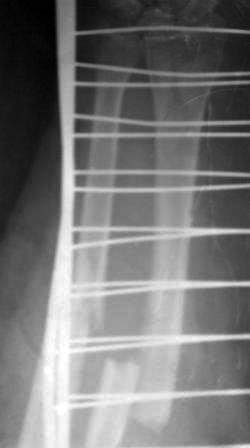

Пациентка 49 лет, по поводу перелома обеих костей предплечья оперирована в марте месяце « и/м остеосинтез спицами», через 4 месяца спицы удалены , антибиотикотерапия и фиксация гипсовой повязкой продолжена, но, учитывая что образуются ложный сустав, госпитализирована.

Повторно открывать зону перелома никак не хочется, учитывая р-картину! А что если закрыто рассверливать к/м канал ( как при БИОС), и КДО аппаратом Илизарова?

Уважаемые коллеги помогите советом! Извиняюсь за плохое качество р-снимков!